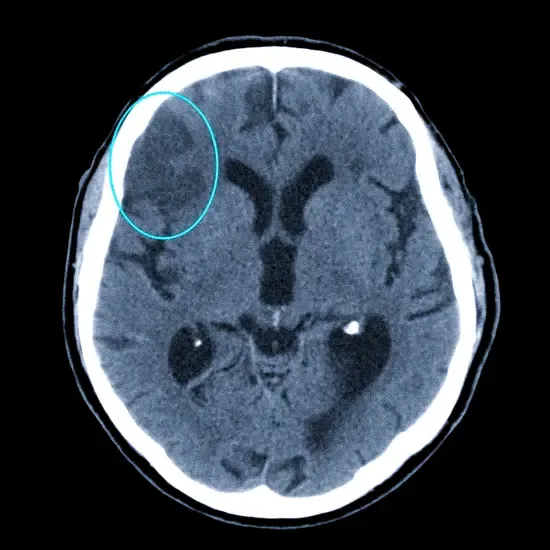

Наша задача состояла в разработке алгоритма, способного анализировать изображения МРТ и оценивать плотность различных тканей. Плотность тканей является важным показателем, который может указывать на наличие опухолей, воспалительных процессов, дегенеративных изменений и других патологий. Например, изменение плотности ткани мозга может быть признаком рассеянного склероза или болезни Альцгеймера.

- Модель U-Net сегментирует изображение МРТ, выделяя различные типы тканей (например, серое вещество, белое вещество, спинномозговая жидкость).

- Для каждой выделенной области вычисляеться среднее значение интенсивности пикселей.

- Среднее значение интенсивности пикселей используется в качестве показателя плотности ткани.

- Полученные значения плотности сравниваются с нормативными значениями, полученными на основе анализа здоровых тканей.

- На основе сравнения выявляются отклонения от нормы, которые могут указывать на наличие патологий.